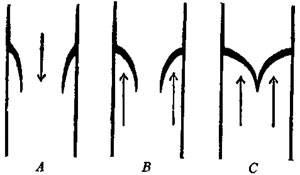

114 Diagram of Artery, Capillaries, and Vein

117 Diagram of Valves in the Veins and Heart